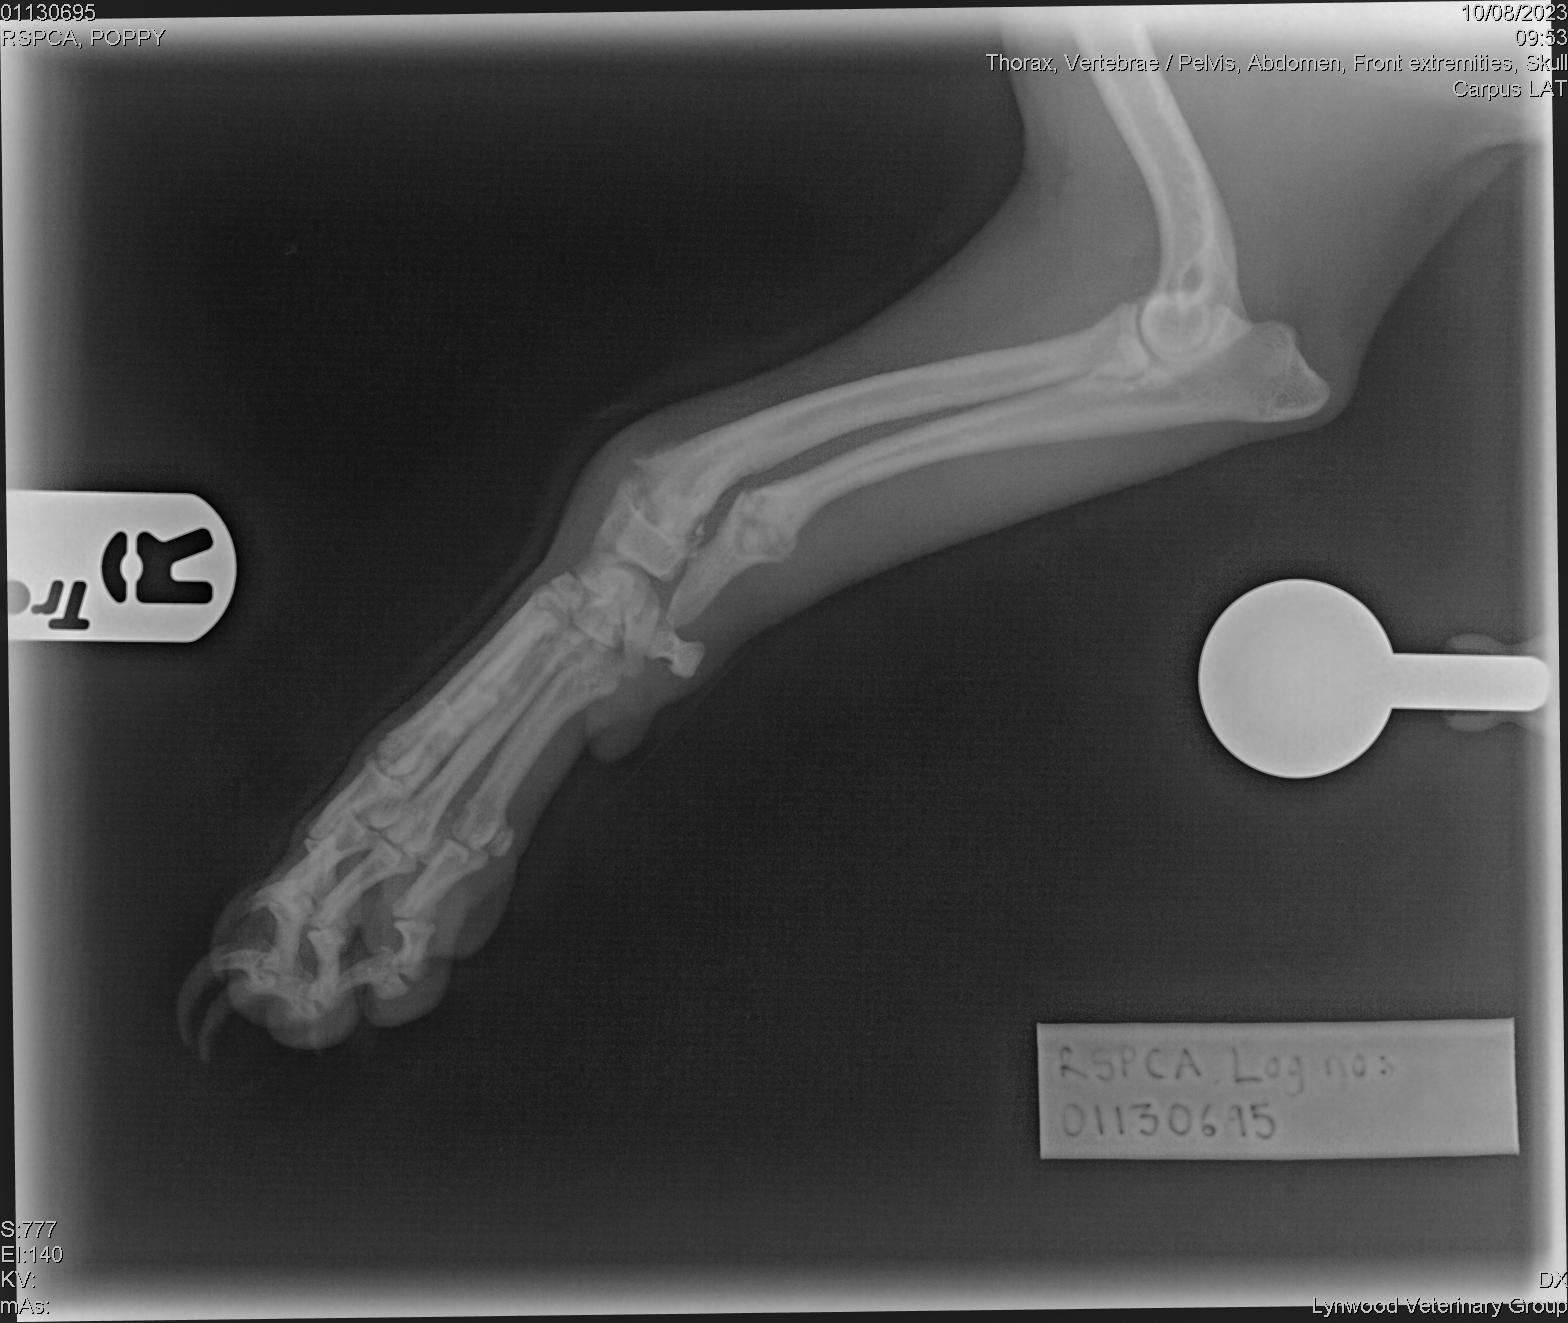

She was rushed for urgent veterinary treatment by the RSPCA where examinations and X-rays found further injuries.

As well as the untreated broken back leg she had two fractures to her right front leg which had started to heal and other historic injuries, including three fractured ribs as well as skin wounds, an amputated ear tip and a cut to her tongue which had since healed.

Some of Poppy’s injuries Picture: RSPCA